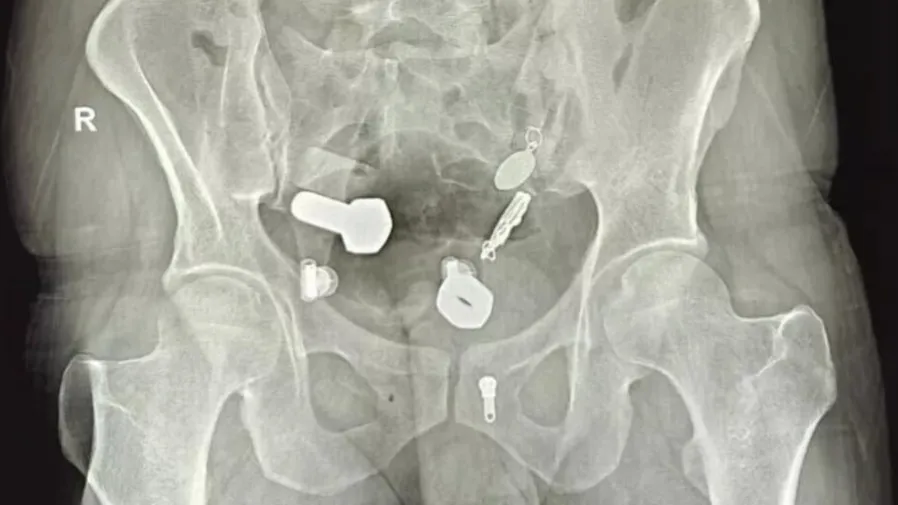

美國加州41歲護士蘇茲羅培茲罹患10公斤卵巢囊腫,備手術時發現懷孕,進一步確診為罕見腹腔妊娠。醫療團隊緊急動員搶救,最終順利接生健康男嬰,書寫生命奇蹟。